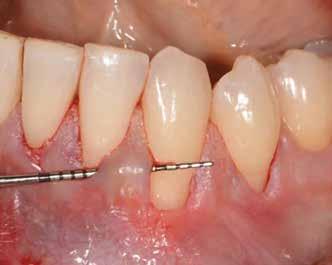

1. ábra: Műtét előtti fogászati panorámafelvétel, amelyen a hiányzó felső állcsont jobb első premolárisát és a szabad véggel rendelkező hidat láthatjuk. — 2. ábra: Az implantátum méreteinek megtervezése CBCT-vel. 3. ábra: Bukkális lágyrészdefektus. — 4. ábra: A biológiai szélesség értékelése a vertikális lágyszövetvastagság alapján. 5. ábra: Palatinális „tekercslebeny” – Palatal roll flap. — 6. ábra: Bredent medical copaSKY 4x10 implantátumbeültetés. 7. ábra: Szubkresztális implantátumbeültetés a várható biológiai szélességnek megfelelően.

8. ábra: Egyéni ínyformázó titánbázison, tulipán alakú emergenciaprofillal. — 9. a. ábra: A sebzárás okkluzális nézete.

bukkális nézete.

(2. ábra). A lágyszövetek értékelése Seibert szerinti I. osztályú csontdefektust állapított meg (3. ábra), ezért a beavatkozáskor palatinális „tekercslebenyt” preparáltunk (palatal roll flap), és implantációt végeztünk, hogy kompenzálni tudjuk a bukkális lágyszövet-behúzódást. Megmértük a vertikális lágyszövetvastagságot, és úgy terveztük, hogy a szubkresztális implantátum beültetése összhangban legyen a biológiai szélesség kialakulásával a transzgingivális gyógyulási periódus alatt (4. ábra)